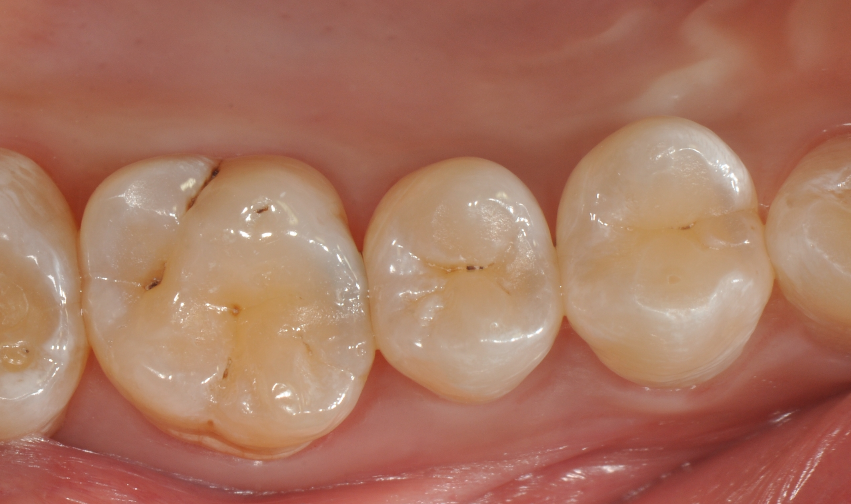

牙医-马小寒【实操病例】

右上6号牙位的近中,可见隐约龋坏

◆去腐完成之后